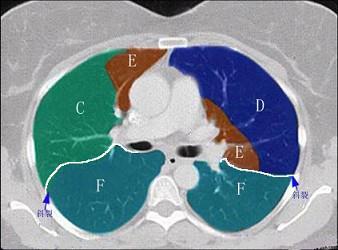

结合肺段模式心室层面(如图),选出右肺上叶的组成 ( )A.AB.A+BC.A+B+CD.A+B+C+DE.A+B+C+D+E

问题 结合肺段模式心室层面(如图),选出右肺上叶的组成 ( )

选项 A.A B.A+B C.A+B+C D.A+B+C+D E.A+B+C+D+E

答案 C